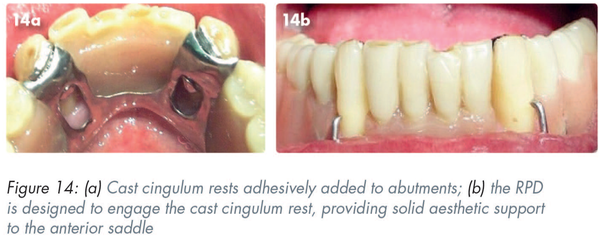

In this example, the cast cingulum rests have been added to abutments adhesively (Figures 14a and 6a). The RPD is designed to engage the cast cingulum rest and thus provide solid aesthetic support to the anterior saddle (Figure 14b).